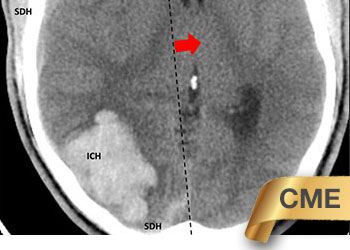

Fig 1. Head CT scan showing large right-sided, parieto-occipital intra-cerebral hemorrhage (ICH) and small occipital and temporal subdural hemorrhage (SDH) with right to left midline shift (red arrow).

A head CT revealed a large posterior-parietal intracerebral bleed, an acute subdural clot, and right to left midline shift (Fig 1). Following the review of a head CTA, the patient was diagnosed with a ruptured brain arteriovenous malformation (AVM). Urgent treatment was indicated for this acute intracerebral hemorrhage (ICH) with significant mass effect and the risk of catastrophic rebleeding of the AVM.